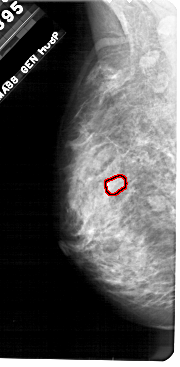

A_1712_1.RIGHT_CC

RIGHT_CC LINES 4921 PIXELS_PER_LINE 2461 BITS_PER_PIXEL 12 RESOLUTION 43.5 NON_OVERLAY

FILE: A_1712_1.LEFT_CC.OVERLAY

TOTAL_ABNORMALITIES 1

ABNORMALITY 1

LESION_TYPE MASS SHAPE OVAL MARGINS OBSCURED

ASSESSMENT 3

SUBTLETY 3

PATHOLOGY BENIGN

TOTAL_OUTLINES 1

BOUNDARY